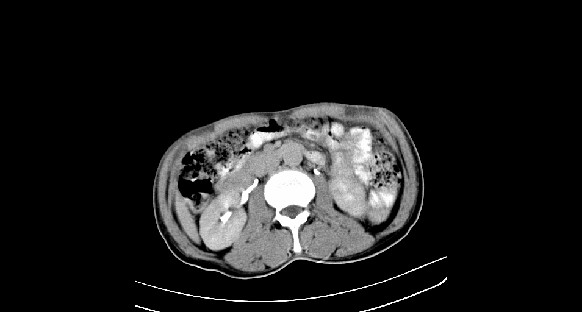

男性,70岁,体检b超发现左肾占位,请各位战友发表一下观点

左肾有两个病灶,且较大的病灶内可见点状钙化灶,增强扫描边缘也是呈渐进性强化,中央部分未见明显强化